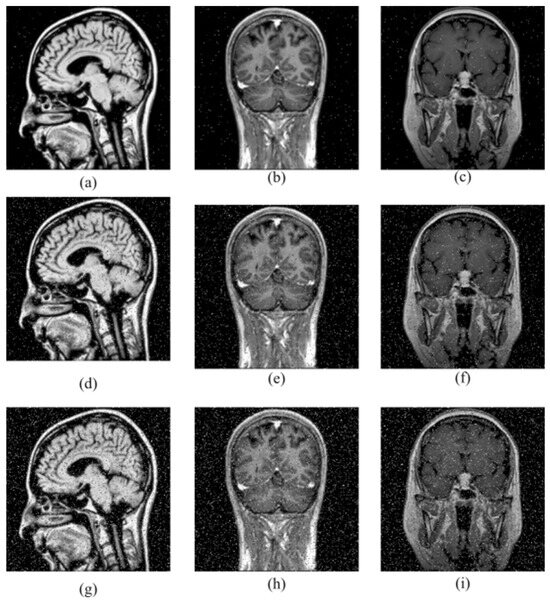

4.2. Histogram Analysis

Histogram analysis reveals the distribution of pixel values of an image. This distribution reflects the characteristics of the image. The histogram of an encrypted image should be completely different from the histogram of the original image. Source images may have different pixel values and colors, so the histogram may show different peaks and a wide distribution. However, since a secure encryption process is achieved by randomizing or secretly scrambling the image data, the histograms of encrypted images should have a more regular and uniform structure [32]. The histogram plots obtained in the study are given in Figure 5.

Figure 5.

Histogram analysis. (a) Source image Img1. (b) Histogram of (a). (c) Encrypted image (a). (d) Histogram of (c). (e) Source image Img2. (f) Histogram of (e). (g) Encrypted image (e). (h) Histogram of (g). (i) Source image Img3. (j) Histogram of (i). (k) Encrypted image (i). (l) Histogram of (k).

Figure 5 shows that the histogram distributions of the encrypted images are in a uniform homogeneous distribution. In order to prove that the histogram of the encrypted image is uniform, an additional chi-square (X2) test was performed. The chi-square value is calculated by the formula given in Equation (4) [33].

For significance level α = 0.05 and degrees of freedom d = 255, the value is 293. The X2 values of the encrypted images are given in Table 3. All of the values obtained are less than 293, indicating that the histogram of the encrypted images is uniform.

Table 3.

Chi-square analysis.